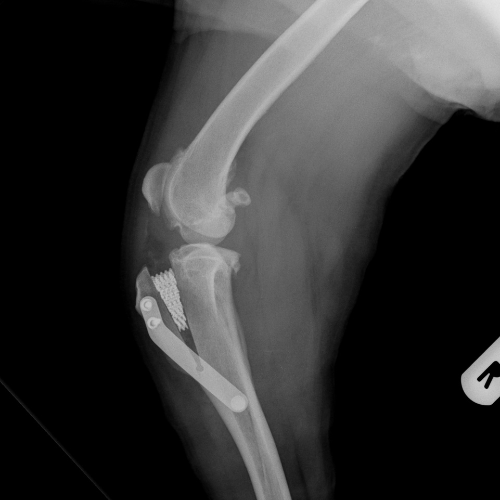

El servicio de traumatología está dirigido por Enrique Senís, especialista en traumatología y ortopedia por la Universidad Complutense de Madrid . Estamos orientados al diagnóstico y tratamiento de patologías del sistema musculoesquelético, incluyendo fracturas, luxaciones, rotura de ligamento cruzado y demás alteraciones articulares y deformidades óseas.

Disponemos de medios diagnósticos avanzados y aplicamos técnicas quirúrgicas de última generación en osteosíntesis, estabilización articular y corrección de deformidades, con el objetivo de restaurar la funcionalidad y minimizar el dolor en nuestros pacientes.